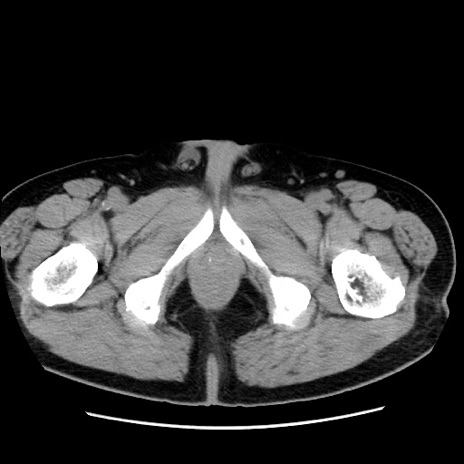

症例16(横断像)

【症例】 70歳代男性

【主訴】 腹痛、嘔吐

【現病歴】 約1ヶ月前より間欠的に腹痛と嘔吐あり、当院消化器内科を受診したところCTで多発する肝臓のLDAを指摘され、精査中であった。以降は消化器症状は安定していたが、2日前より嘔気と腹痛があり、同日より排便・排ガスが消失した。改善認めず、 本日、救急外来を受診した。

【既往歴】 大腸ポリープ切除後。

【身体所見】意識清明・会話良好、BT 36.3℃、BP 127/80mmHg、 P 80bpm、腹部:膨満あり、平坦・軟、上腹部正中および下腹部正中に圧痛あり、反跳痛なし、筋性防御なし。

【データ】WBC 7200、CRP 0.77